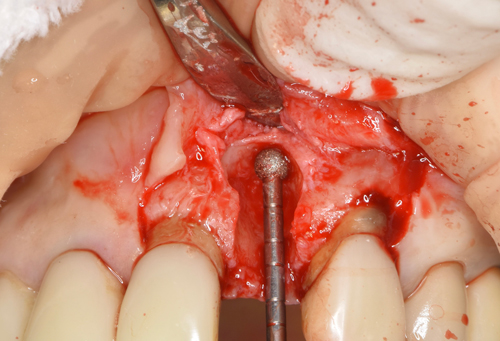

腫瘍摘出ドリルで骨に付着している肉塊を徹底的にはく離させます。

唇側の半分がほとんど骨が失われていました。この状態からインプラントを移植して、不足している骨も同時に再生定着

させていきます。